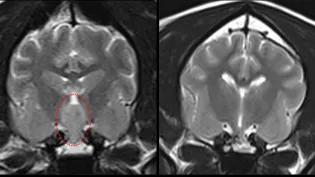

Spaniel makes full recovery after tumour is removed through the top of his mouth. Vets at the Hospital for Small Animals have performed a challenging surgery to remove a dog’s brain tumour.In the complex procedure, veterinary neurosurgeons removed a large mass from the base of a Spaniel’s brain, through a small hole in the top of his mouth. The Hospital is the first in Scotland, and one of only five centres in the UK, that has successfully performed surgery of this kind in dogs. It is also one of a handful in Europe that offer both radiotherapy and surgery as treatment options for cats and dogs with tumours of this type. Complex caseLordy, an eight-year-old cocker spaniel, was referred to the Hospital’s Neurology Service with multiple complex neurological problems.An MRI scan identified a large tumour on Lordy’s pituitary gland, at the base of his brain. Further tests confirmed that Lordy also had Cushing’s syndrome, a potentially fatal condition involving over-production of a key hormone, due to the mass. Magnetic Resonance Imaging (MRI) of Lordy’s brain before (left) and after (right) surgery. The pituitary tumour is encircled (red). Specialist surgeryA follow-up CT scan suggested that the tumour was growing and could invade other parts of Lordy’s brain and spinal column, which could lead to additional problems. In consultation with the dog's owners, it was agreed that the best option for Lordy was for vets to surgically remove the tumour in a procedure known as a transsphenoidal hypophysectomy. In preparation for this technically challenging surgery, a 3D-printed model was produced using CT images of Lordy’s brain and tumour. This was fitted onto the roof of Lordy’s mouth during surgery, to help the vets locate the best access point to locate the tumour during the operation. Surgeons then drilled a 5mm hole through Lordy’s soft palate and the base of his skull, allowing them to access and remove the tumour.Positive outcome Lordy was under the watchful eye of the Hospital’s Anaesthesia and Emergency and Critical Care Services both during and after surgery. The spaniel recovered quickly and was discharged three days later. Follow-up MRI scans three and six months later showed no sign of the tumour or damage to brain tissues. Lordy remains a regular visitor to the Hospital’s Internal Medicine Service, for continued monitoring and care. We are pleased that Lordy’s surgery was a success. His care required a multidisciplinary approach and involved colleagues from the Anaesthesia, Internal Medicine and Emergency Critical Care Services at the Hospital. Dr Aran Nagendran Co-Head of Neurology Service and Specialist in Veterinary Neurosurgery, Dick Vet Hospital for Small Animals. We are delighted that Lordy’s Cushing’s syndrome has been resolved due to this surgery. He has made great progress since his operation and we are happy to supply ongoing care. Dr Alisdair Boag Specialist in Small Animal Medicine, DicK Vet Hospital for Small Animals We are eternally grateful to everyone involved in Lordy’s care. Since his surgery he has bounced back to be the same energetic little monster he was as a young dog, bringing us love and joy every day. Lordy’s owners About the Royal (Dick) School of Veterinary Studies The Royal (Dick) School of Veterinary Studies is a one-of-a-kind centre of excellence in clinical activity, teaching and research. Our purpose-built campus, set against the backdrop of the beautiful Pentland Hills Regional Park, is home to more than 800 staff and almost 1400 students, all of whom contribute to our exceptional community ethos. The School comprises: The Roslin Institute The Roslin Innovation Centre The Hospital for Small Animals Equine Veterinary Services Farm Animal Services Easter Bush Pathology The Animal Welfare Centre We represent the largest concentration of animal science-related expertise in Europe, impacting local, regional, national and international communities in terms of economic growth, the provision of clinical services and the advancement of scientific knowledge. Tags Small Animals Publication date 10 Mar, 2025